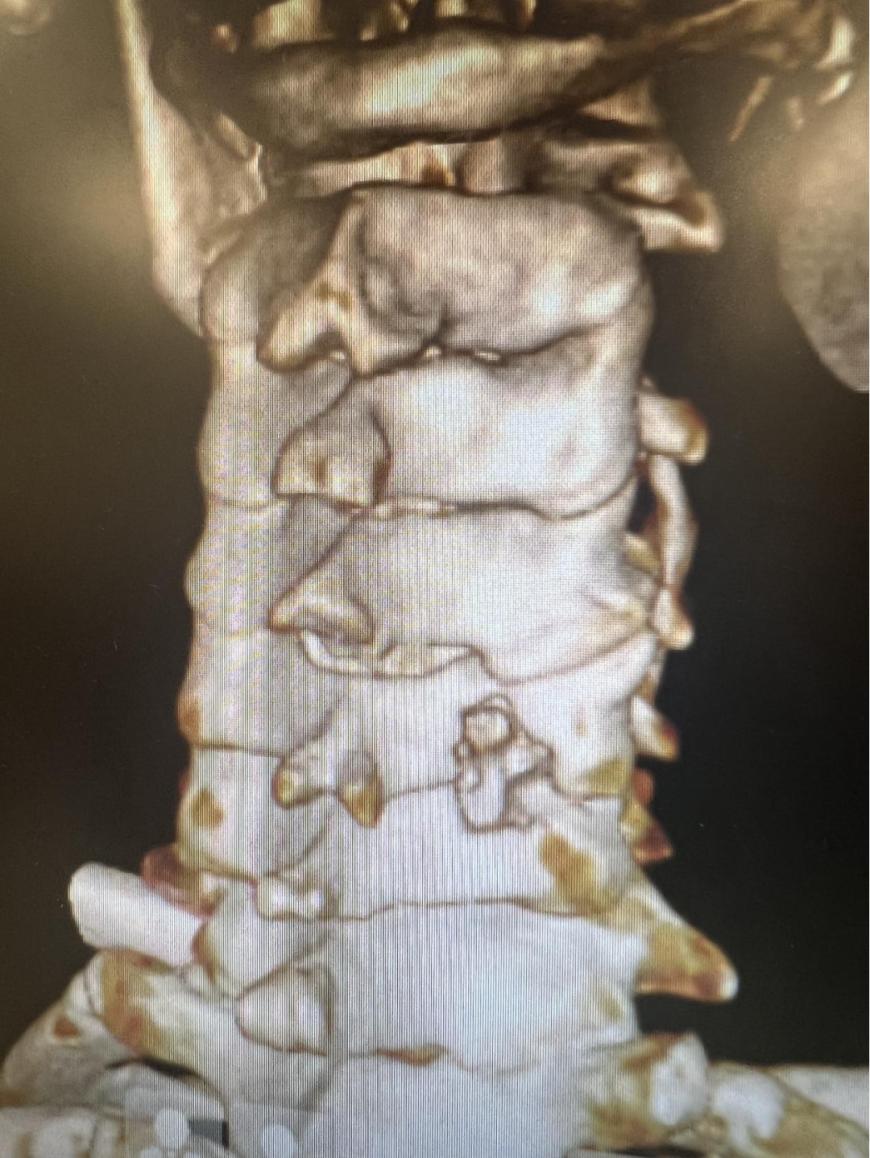

近日,西安市红会医院腰椎病区杨俊松副主任医师在脊柱病医院院长郝定均、脊柱病医院腰椎病区主任刘团江的指导下完成一例超声骨刀辅助脊柱内镜下Keyhole减压治疗骨性颈椎间孔狭窄,标志着西安市红会医院脊柱微创手术治疗水平再上新高。

杨俊松副主任医师接诊后结合患者病史、体征和影像学资料指出,患者椎间盘突出钙化形成骨赘+神经根明显受压+椎间孔高度塌陷,建议手术干预。

脊柱病医院院长郝定均及脊柱病医院腰椎病区主任刘团江查房后指出:患者骨赘生长及神经根受压明显,且曾有过两次甲状腺手术经历,建议采用内镜下的颈椎后路keyhole手术。

手术结束后当天患者症状明显缓解。复查影像资料显示神经减压良好、骨赘完全去除。

术后影像资料